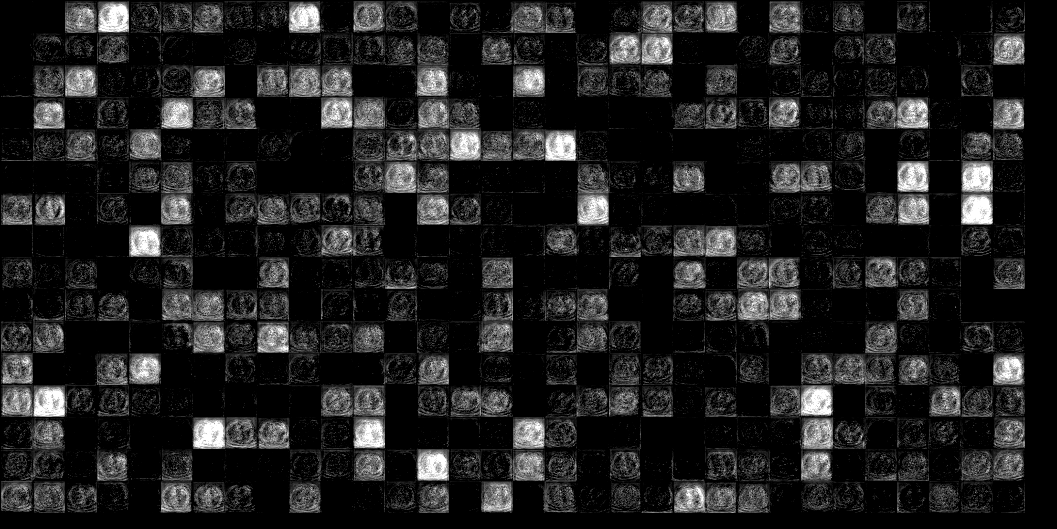

Since VGG network is trained on natural images, it may cause concerns on how well it performs on CT image feature extraction. Thus, we displayed two feature maps of normal dose and quarter dose images and their absolute difference in Fig. 9. The feature map contains 512 small images of size . We organize these small images into a array. Each small image emphasizes a feature of the original CT image, i.e. boundaries, edges, or whole structures. Thus, we believe VGG network can also serve a good feature extractor for CT images.